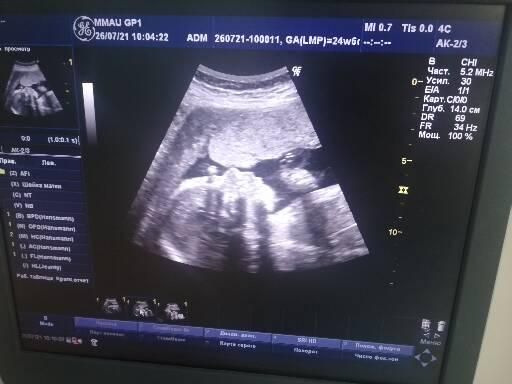

А самое главное, мы были на узи контроле, кисточки рассосались и это невероятное счастье 😻😻😻 малыш живёт в своём домике, милашка такой, показывал кулачки и обсасывал палец😂😂😂😻😻 Моё сокровище. И врач попалась просто душка, разрешила даже снять этот момент на видео🙏🙏🙏

Фото на память🤰💫